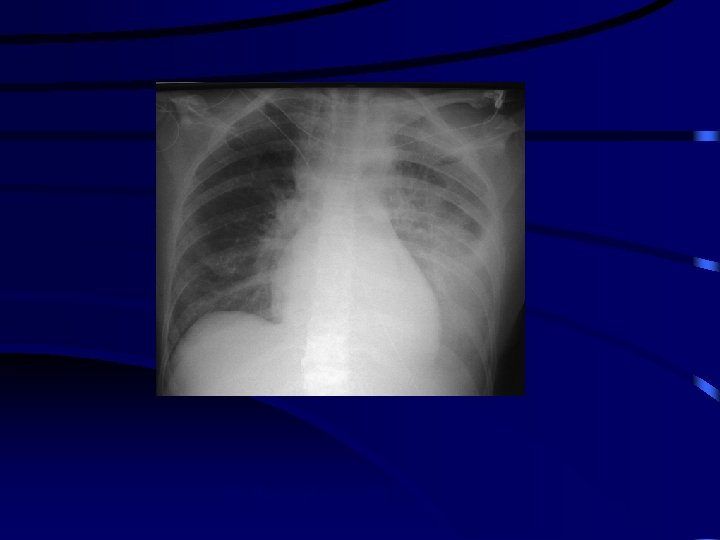

lungmetastasis Rx thorax Ct scan biopsy

RX thorax pleuravocht